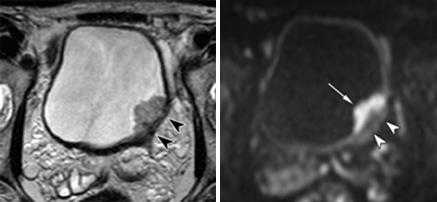

Неинвазивная папиллярная уротелиальная опухоль. Корональное Т2-взвешенное МР- изображение показывает тканевой интенсивности сигнала опухоль (стрелка),растущая в просвет мочевой\го пузыря. При бесконтрастном исследовании создается впечатление о сохранности прилежащих отделов гипоинтенсивной стенки мочевого пузыря. Однако достоверно судить о степени глубины инвазии можно только по постконтрастным сканам.

При этом важно проведение именно динамического внутривенного контрастирования (в артериальную фазу происходит усиление только ткани опухоли, но еще не успевает произойти усиление интактной стенки мочевого пузыря). На представленном контрастном Т1-ВИ изображении (артериальная фаза) на фоне накопления КВ тканью опухоли, подслизистого слоя, видно отсутствие инвазии прилежащей стенки мочевого пузыря.